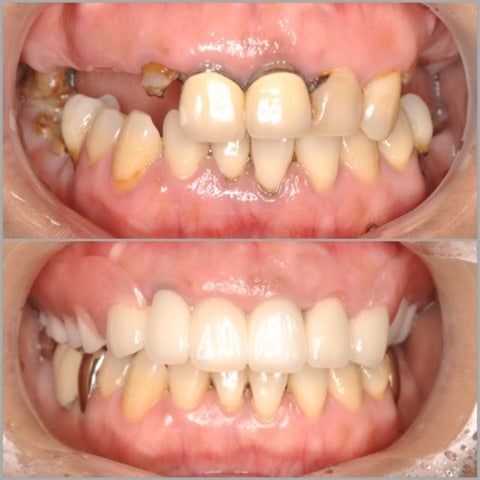

<before/after>

笑顔も生き生きとし、私としても患者様の人生を変えることができた事を嬉しく思います。

しっかりとカウンセリングを行い、患者様のお気持ちを考えた上で治療経計画を立案し、無痛リラクゼーション治療による治療を行いました。

目立つところはセラミックを用い、目立たない部分は健康保険を使用し、可能な限り患者様のコスト的負担を減らすように工夫しました。